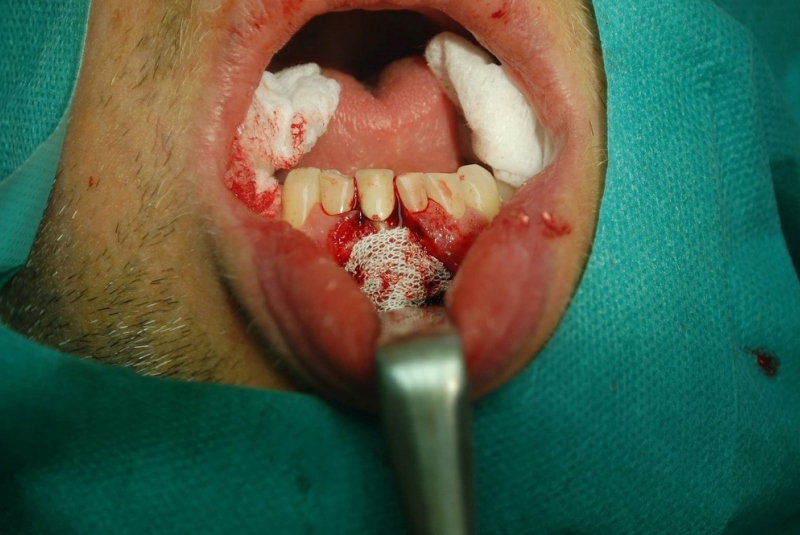

- Resekcia (odstránenie zápalového ložiska zubného pôvodu)

- Excízie (odsránenie patologických ložísk, vrátane histologického vyšetrenia)

- Prehĺbenie plytkého vestibula

- Plastiky (rôzneho rozsahu)